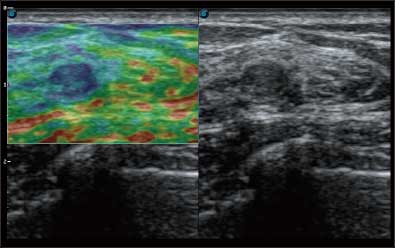

• 弹性成像

全新算法处理射频信号 不可靠区域自动剔除 支持定量分析 压力曲线保证重复性

• Wi-Flow

通过对组织运动信息、血流信号及背景噪声进行准确智能的阈值判定,高效提取出微弱血流信号,获得高灵敏度和空间分辨率的血流图像,为临床提供更加真实和丰富的诊断信息。